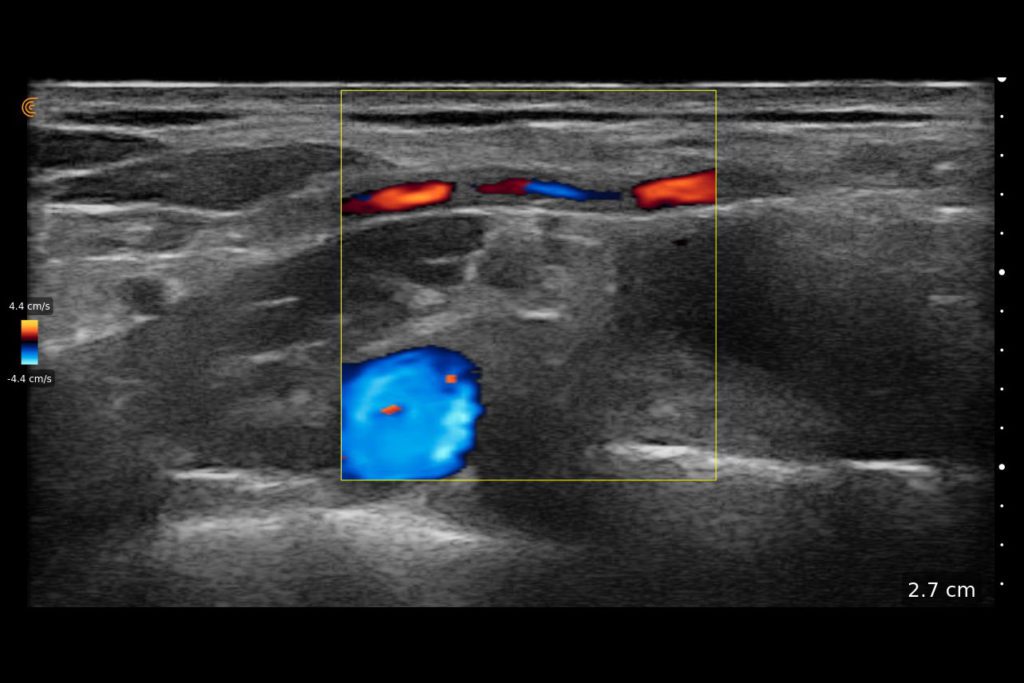

With high-definition imaging comparable to traditional systems, Clarius is the ultimate wireless ultrasound scanner for safe regional nerve blocks and post-operative follow-up.

Now with our wireless Clarius Ultrasound Scanner, we can connect to our iPads and iPhones very easily and take it with us anywhere.